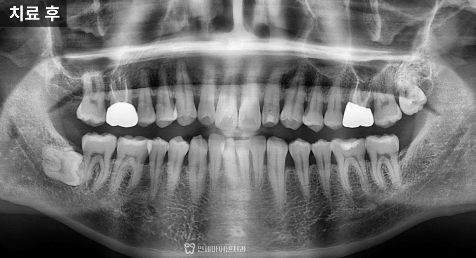

이 과정을 거쳐 크라운을 다시 제작했고,

현재는 씹을 때 불편감 없이

안정적으로 사용 중입니다.

반대편 어금니도 미리 점검한 이유

반대편 어금니는 구조와 치료 방식이

유사하다는 점을 고려해

똑같이 치료를 진행했습니다.

아프지 않더라도 내부 구조가

취약하다면 동일한 문제가 반복될

가능성이 있기 때문입니다.